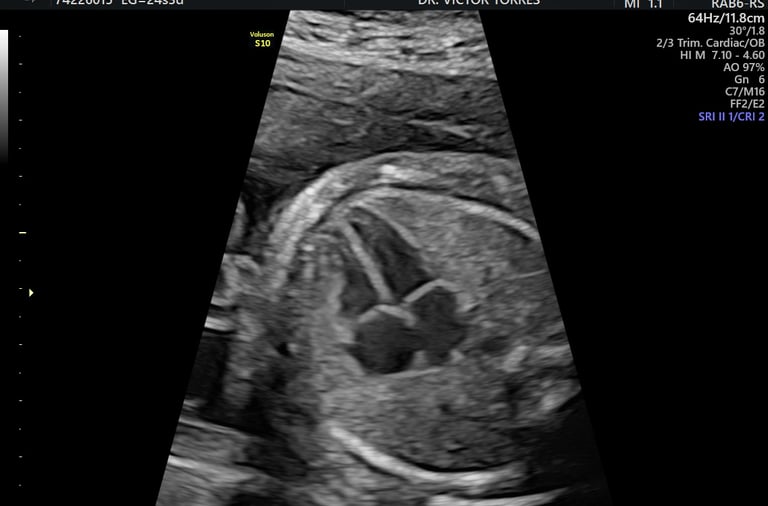

ecocardiografía fetal